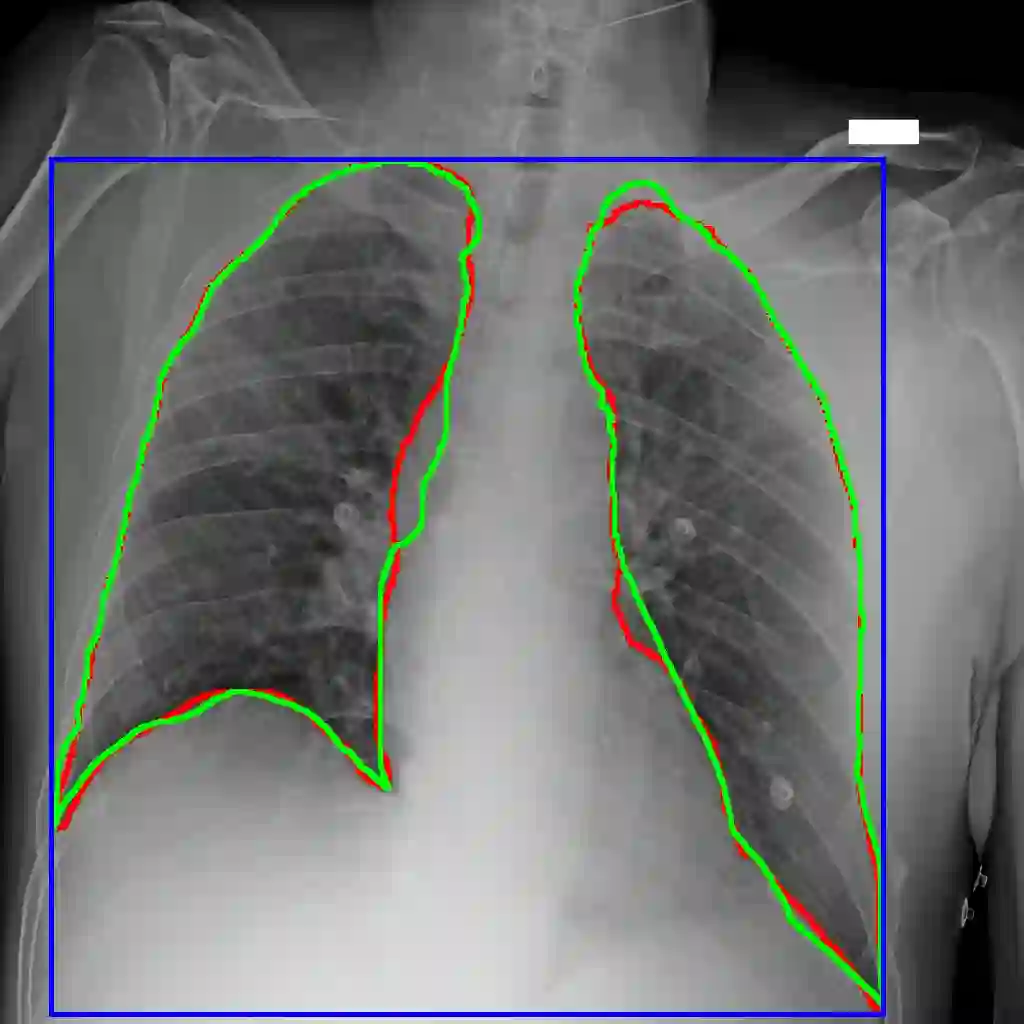

Recent epidemiological data report that worldwide more than 53 million people have been infected by SARS-CoV-2, resulting in 1.3 million deaths. The disease has been spreading very rapidly and few months after the identification of the first infected, shortage of hospital resources quickly became a problem. In this work we investigate whether chest X-ray (CXR) can be used as a possible tool for the early identification of patients at risk of severe outcome, like intensive care or death. CXR is a radiological technique that compared to computed tomography (CT) it is simpler, faster, more widespread and it induces lower radiation dose. We present a dataset including data collected from 820 patients by six Italian hospitals in spring 2020 during the first COVID-19 emergency. The dataset includes CXR images, several clinical attributes and clinical outcomes. We investigate the potential of artificial intelligence to predict the prognosis of such patients, distinguishing between severe and mild cases, thus offering a baseline reference for other researchers and practitioners. To this goal, we present three approaches that use features extracted from CXR images, either handcrafted or automatically by convolutional neuronal networks, which are then integrated with the clinical data. Exhaustive evaluation shows promising performance both in 10-fold and leave-one-centre-out cross-validation, implying that clinical data and images have the potential to provide useful information for the management of patients and hospital resources.